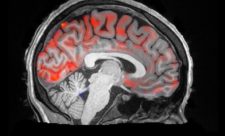

סורקי ה-MRI, המשמשים ככלי אבחון ומחקר, קיימים בעולמנו כבר כארבעה עשורים, מאז התקנתו והפעלתו של סורק ה-MRI הראשון ...

סורקי ה-MRI, המשמשים ככלי אבחון ומחקר,...